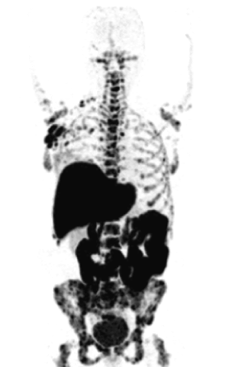

S.R.Y. is a subsidiary of Hadassah Ein Karem hospital. The company specializes in developing and producing radiopharmaceuticals, and it is the only company in Israel that has clean rooms and cyclotron facilities (particle accelerators) with eight automatic modules for synthesizing different kinds of radioisotopes (cyclotron products).

The new production rooms cost about 13 million shekels. S.R.Y.’s products are supplied for PET scans both to Hadassah Ein Karem hospital and to several hospitals throughout the country, including Assuta, Beilinson, Sheba, Ichilov, and Shaare Zedek.